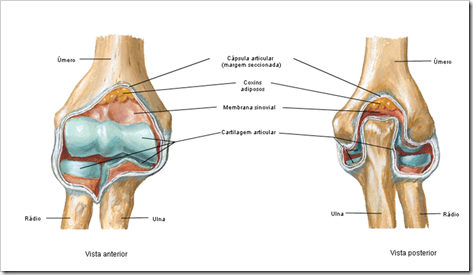

Articulações sinoviais (amplo movimento)

*Componentes anatômicos (elementos):

>Cápsula articular: envolve a articulação

>>Membrana fibrosa: externa

>>Membrana sinovial: interna

Cavidade articular:espaço entre os ossos

Cartilagem articular: apresenta cartilagem hialina

Discos e meniscos: fibrocartilagens intra-articulares

*Ligamentos: união e limitação de movimento

>Intra-capsulares

>Extra-capsulares